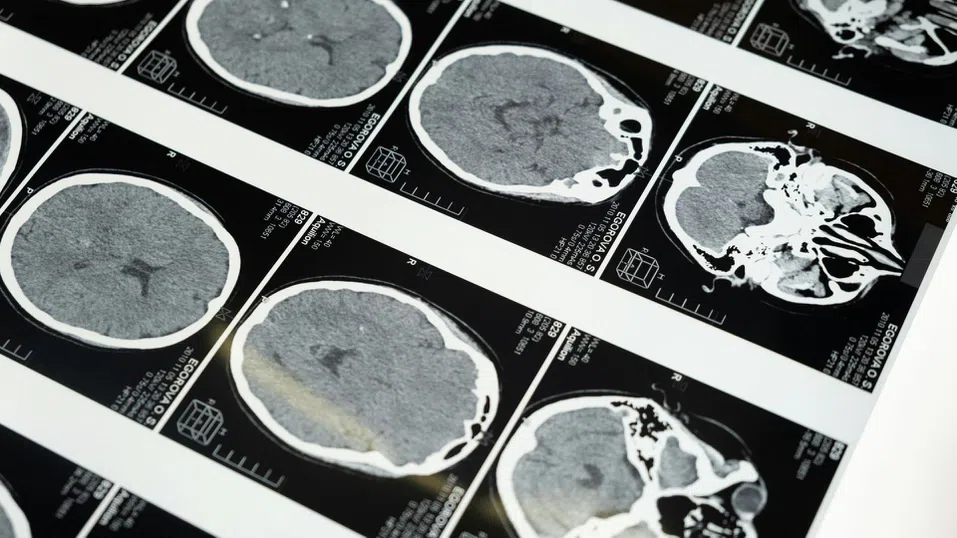

Инсултът е една от водещите причини за дългосрочна инвалидност, като приблизително две трети от преживелите го пациенти страдат от сериозни нарушения в движенията на ръцете. Част от тях възстановяват функциите си с времето, но при много хора слабостта или парализата остават постоянни.

В основата на тази технология стои концепцията за невропластичност – способността на мозъка да създава нови връзки. При инсулт част от мозъка се уврежда заради липса на кислород, което блокира сигналите към мускулите.